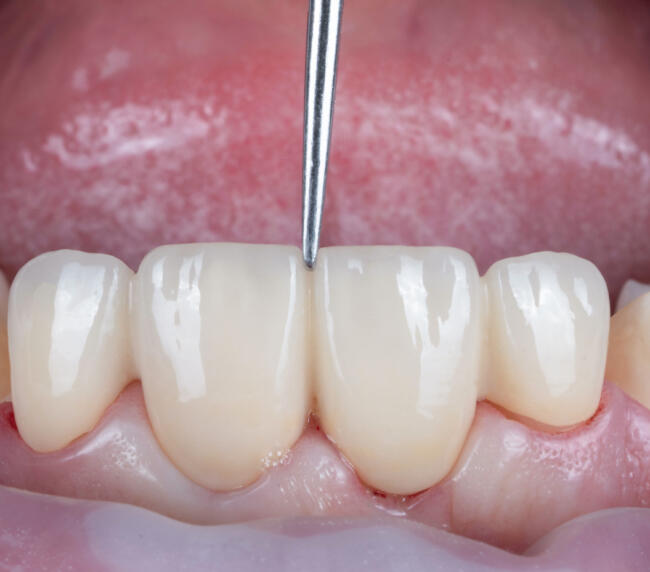

- Proba lucrării și adaptarea funcțională și estetică

- Fixarea definitivă cu ciment special